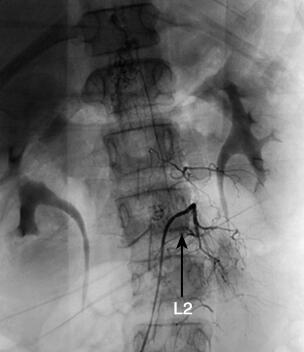

诊疗经过:入院后行腰椎穿刺术,连续留取3管脑脊液,均为淡红色血性脑脊液,脑脊液化验结果除外中枢神经系统感染。2010年10月28日晚19时40分患儿站立中诉腿疼,平卧后再次出现抽搐,表现为口吐白沫、双手握拳、双上肢屈曲、颈部强直,并有意识障碍。予吸氧、镇静止惊、改善脑水肿等对症治疗,仍反复抽搐多次。急诊行颅脑CT检查,示脑室及蛛网膜下腔少量出血(图3)。遂由儿内科转神经外科治疗。转科后行全脑全脊髓血管造影提示:T11~L2脊髓血管畸形(图4)。遂于2010年11月10日在全麻下行T11~L2脊髓畸形血管团切除+椎板扩大成形+硬膜修补术。术后给予脱水、抗炎、止血、补液、支持、神经营养、激素等治疗后患者意识逐渐转清,未再抽搐,病情稳定出院。

图4 全脑全脊髓血管造影(2010年10月29日)提示:T11~L2硬脊膜动静脉瘘(箭头)

本例入院前反复抽搐起病,考虑每次出血量不多,随着出血吸收,症状缓解。入院后根据患儿脑膜刺激征、血性脑脊液及颅脑CT检查不能除外蛛网膜下腔出血。行全脑血管造影术未发现颅内血管畸形,继续向下行脊髓血管造影证实为胸腰段脊髓血管畸形致脊髓蛛网膜下腔出血并反流入脑室系统和蛛网膜下腔导致抽搐和意识障碍。

根据血管造影的表现,通常将脊髓血管畸形分为4型:髓内动静脉畸形、膜内髓周动静脉瘘、硬脊膜动静脉瘘和混合型动静脉畸形[3]。临床上以硬脊膜动静脉瘘最常见,是指在神经孔处硬脊膜上多发的动静脉瘘,动脉供血主要来源于节段性动脉的硬膜分支,静脉回流至脊髓的冠状静脉丛,静脉引流主要位于脊髓背侧,可贯穿脊髓全长。发病机制主要为静脉高压引起脊髓及神经根淤血、水肿。脊髓盗血、血栓形成、畸形血管局部占位、静脉高压以及出血均可有如下表现:后背及神经根痛、截瘫、横贯性感觉障碍、括约肌功能及性功能障碍,而蛛网膜下腔出血、腹壁牵涉痛等少见[4]。本例患儿脊髓血管造影表现符合硬脊膜动静脉瘘,之所以无截瘫等表现,可能与出血量少、畸形血管团尚未对脊髓造成明显压迫有关。